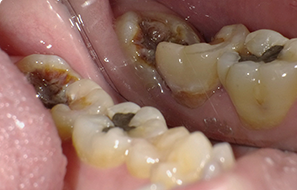

外面拔時易斷裂於骨頭內而難以取出